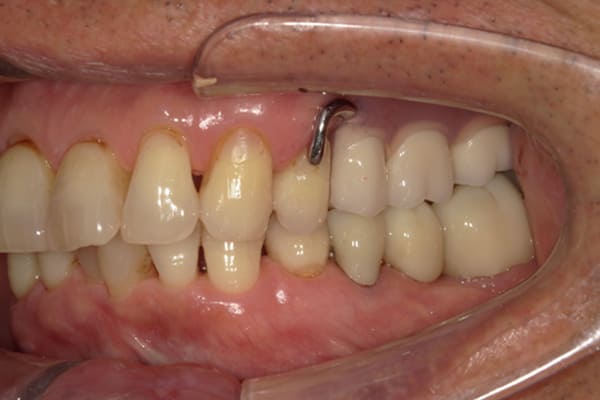

症例レポート[CASE.02]

入れ歯がカパカパして痛い、

歯がぐらぐらする

- 性別・年齢

- 男性(60代)

- 主訴

- 入れ歯がカパカパする、歯がぐらぐらして痛い、食いしばれない

- 治療

-

- 上顎精密総金属床総入れ歯

- 下顎精密金属床部分入れ歯

- ジルコニアクラウン4歯

- 治療期間

- 約3か月間

- 費用

- 上顎精密総金属床総入れ歯:55万円

- 下顎精密金属床部分入れ歯:55万円

(ミリング、ラベット加工込み) - ジルコニアクラウン:11万円×4歯

合計:154万円(税込)

上の前歯が重度歯周病により動揺し、残せない状態のため、入れ歯も動揺がありました。

ご自身の歯に負担の少ないバネ、また見た目も改善

バネをかける歯は繋げることで強度を増し、歯への負担を軽減し、歯の寿命を長くする設計へ。

バネがかかる歯の被せ物は、歯への負担を減らし、入れ歯が動きにくいようになる形態をあらかじめ付与することで、より入れ歯の機能が高まります。

治療を行う際、被せ物や入れ歯は、別々に考えるのではなく、一口腔単位としてお口全体のことを考え最良の治療計画を立てることが歯の寿命、機能効果を向上させるため、専門医としてこのことは常に心掛けて治療を行っています。